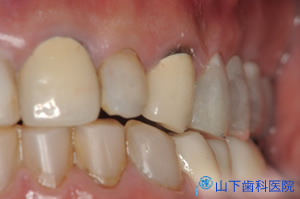

| 右側からの側貌観 |

![]() |

| 左側からの側貌観 | ![]() |

アメリカを始め諸外国に行っても日本人として恥ずかしくない、自信を持って歯を見せるスマイルが若々しさと自信を取り戻したと 結果にとても満足して頂けました。

咬み合せを挙げ、咬み合せ形態を完全に作り直していますが、噛む機能には全く影響がなく、とても良く噛めるそうです。